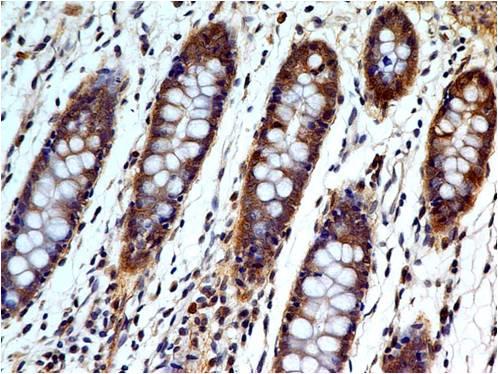

Figure 1: Formalin-fixed, paraffin-embedded human Urothelial Carcinoma stained with p21 Rabbit Recombinant Monoclonal Antibody (CIP1/2275R).

This MAb recognizes a 21kDa protein, identified as the p21WAF1 tumor suppressor protein. This MAb is highly specific to p21 and shows no cross-reaction with other closely related mitotic inhibitors. p21WAF1 is a specific inhibitor of cdk s and a tumor suppressor involved in the pathogenesis of a variety of malignancies. The expression of this gene acts as an inhibitor of the cell cycle during G1 phase and is tightly controlled by the tumor suppressor protein p53. Its expression is induced by the wild type, but not mutant, p53 suppressor protein. Normal cells generally display a rather intense nuclear p21 expression. Loss of p21 expression has been reported in many carcinomas (gastric carcinoma, non-small cell lung carcinoma, thyroid carcinoma).

Western Blot (1-2µg/ml); Immunohistochemistry (Formalin-fixed) (1-2µg/ml for 30 minutes at RT)(Staining of formalin-fixed tissues requires heating tissue sections in 10mM Tris with 1mM EDTA, pH 9.0, for 45 min at 95°C followed by cooling at RT for 20 minutes);